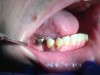

Fig 7 through Fig 9. This young patient’s only prosthetic option was extraction of all remaining teeth and subsequent placement of complete dentures.

In Figure 7 through Figure 9, the young woman shown had many adverse childhood experiences and was given methamphetamine by an adult when she was 14 years old. She also had her first child at that age, and then had three more children while addicted to meth, though she was only able to retain custody of one of her children. In addition to alcohol, she used meth for 15 years. Her only prosthetic option was extraction of all of her remaining teeth and subsequent placement of complete dentures.